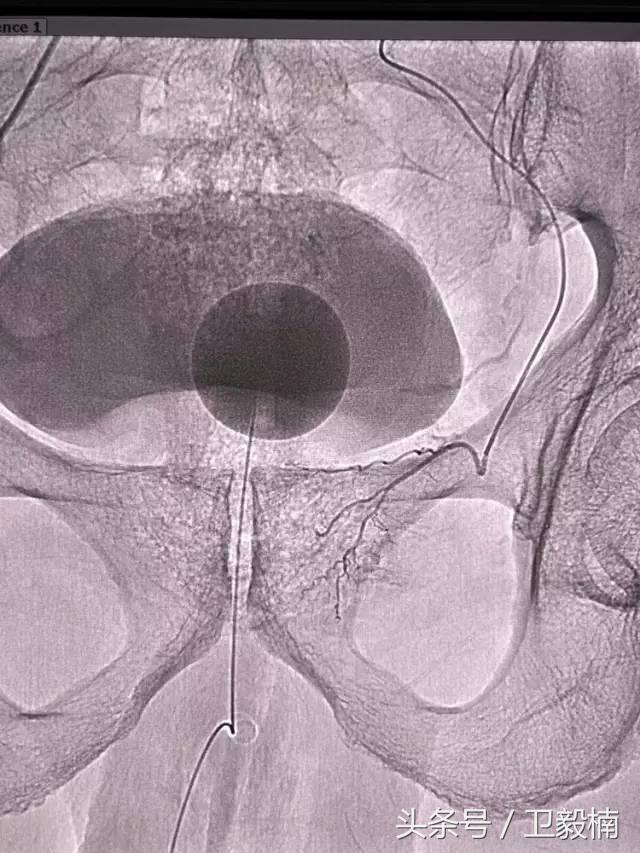

五、出血性疾病:鼻腔大出血、咯血、上消化道大出血、经皮肾镜术后出血、膀胱出血、产后出血等

(3)应用栓塞材料,钢圈,内支架治疗动脉瘤、AVM、动静脉瘘,血管性出血。

(5)应用栓塞术或血管加压素治疗胃肠道血管出血。

(3)应用栓塞术治疗海绵状血管瘤,蔓状血管瘤,子宫肌瘤,骨肉瘤,鼻咽部纤维血管瘤等。